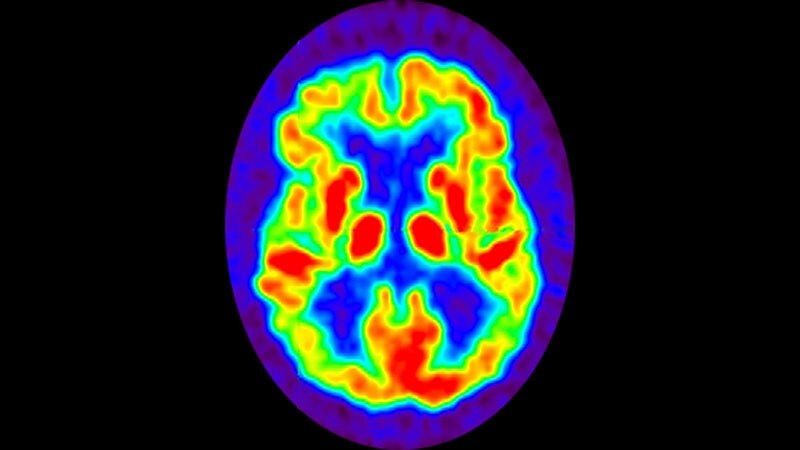

Alzheimer's Disease